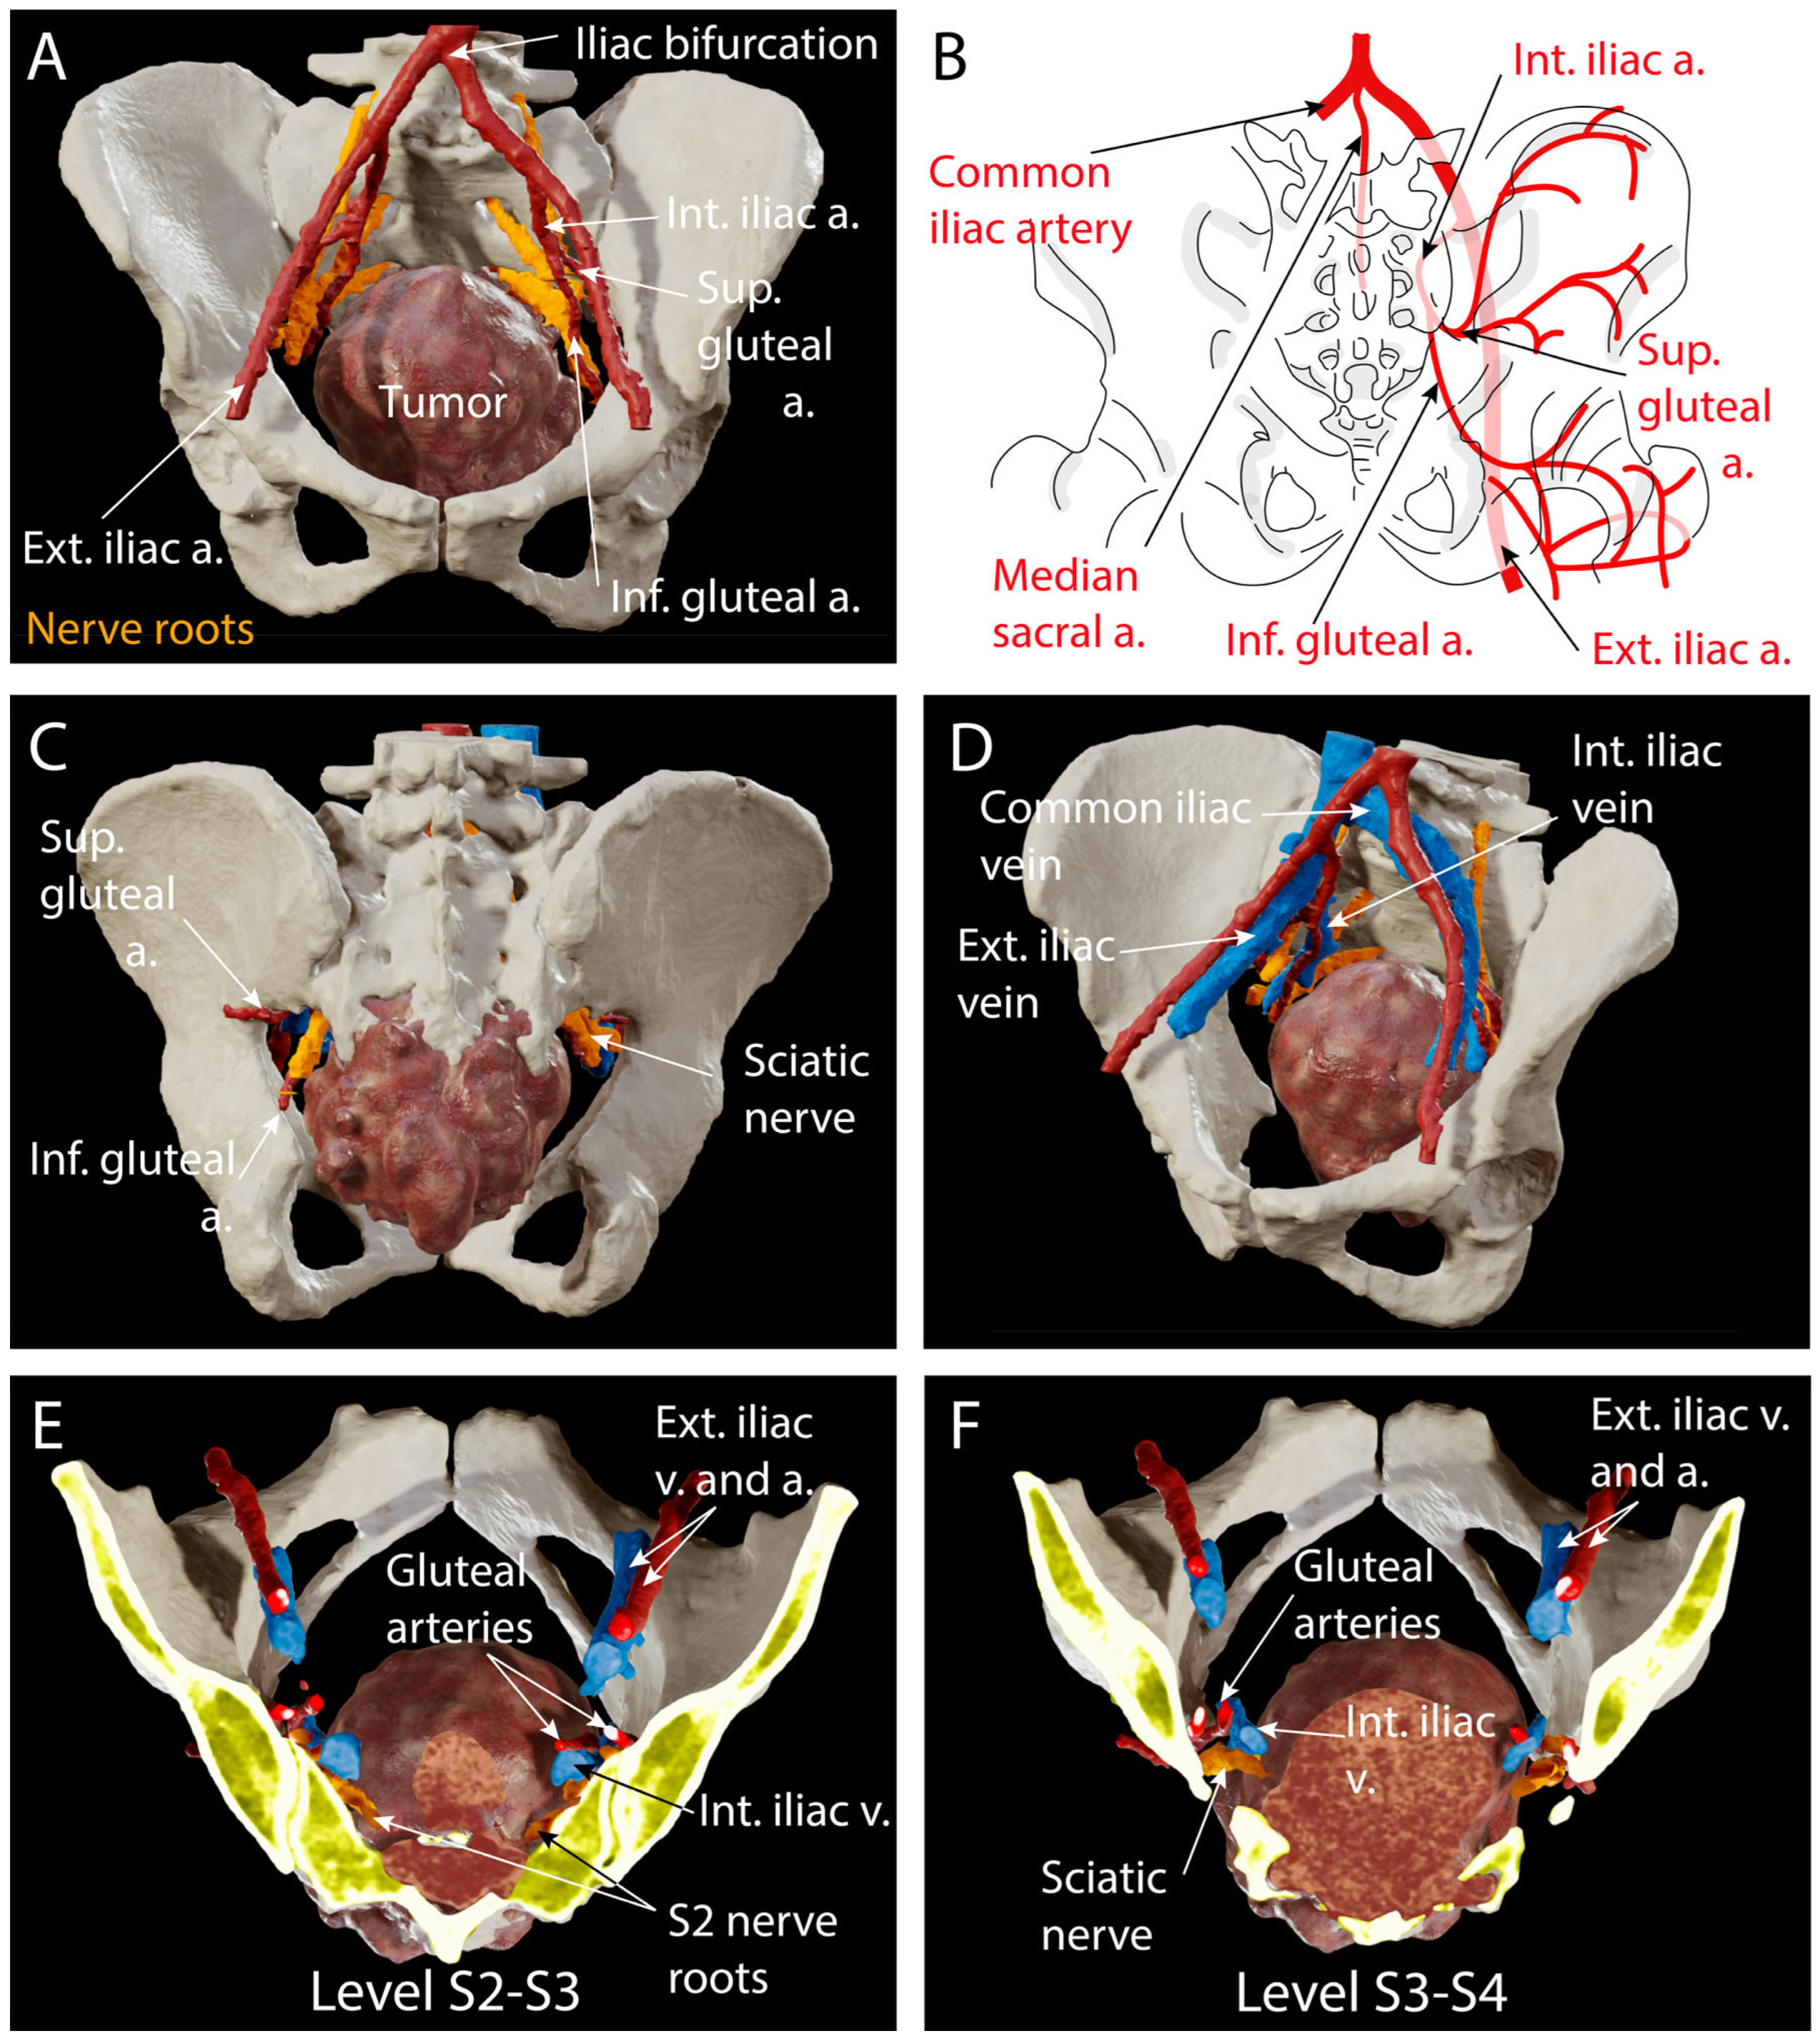

4.2. Preoperative Planning

4.3. Surgical Technique